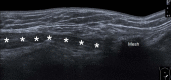

Inguinal hernia is the most prevalent type of abdominal wall hernia. Indirect inguinal hernia is twice as common as direct inguinal hernia. Computed tomography and magnetic resonance imaging can be used to evaluate inguinal hernia, but these modalities are greatly limited by their cost and availability. Ultrasonography has emerged as the most convenient imaging tool for diagnosing inguinal hernia due to its advantages, such as portability and absence of radiation. The present pictorial review presents an overview on the use of ultrasonography in the evaluation of inguinal hernia with a particular emphasis on the regional anatomy, relevant scanning tips, identification of subtypes, postoperative follow-up, and diagnosis of pathologies mimicking inguinal hernia.